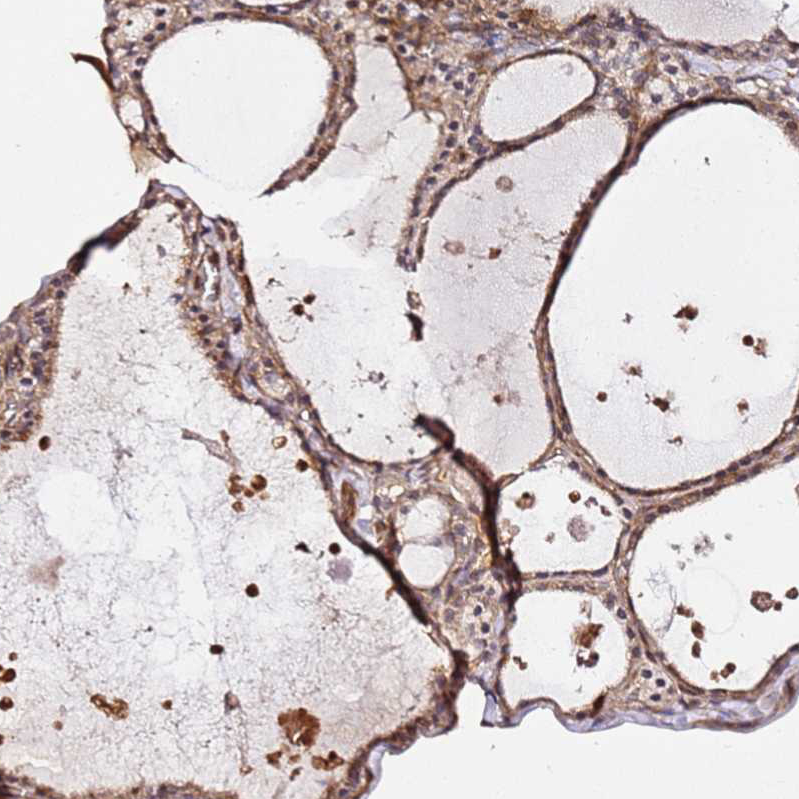

Immunohistochemical staining of human thyroid gland shows strong cytoplasmic positivity in glandular cells.